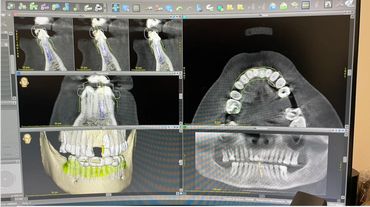

Where and how to use 2.9 Narrow implant